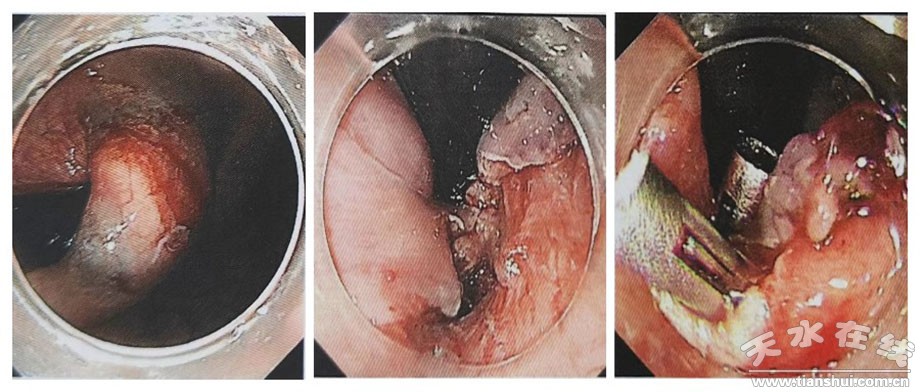

7月4日13:30在市一院內(nèi)鏡中心和麻醉科的協(xié)助下,進(jìn)行全身麻醉+氣管插管,手術(shù)過程中,在蘭大一院姬瑞主任醫(yī)師的指導(dǎo)下,消化內(nèi)科茍金平主任醫(yī)師、贠嘉威主治醫(yī)師、張云主治醫(yī)師及內(nèi)鏡室護(hù)士的協(xié)調(diào)配合下,在內(nèi)鏡下使用Dual-knife切開腫瘤表面黏膜層,暴露白色瘤體,后沿黏膜下層剝離瘤體,并予以圈套器、活檢鉗輔助牽引完整挖除瘤體,剝離過程中出現(xiàn)穿孔,予以9枚鈦夾封閉創(chuàng)面。患者右側(cè)胸壁、顏面部可觸及捻發(fā)感,遂啟動多學(xué)科協(xié)作(MDT),請胸外科、超聲科、放射科、重癥醫(yī)學(xué)科等多學(xué)科專家術(shù)中會診,考慮皮下氣腫。術(shù)中嚴(yán)密觀察患者,生命體征平穩(wěn),手術(shù)成功,實現(xiàn)了以最小創(chuàng)傷達(dá)到最佳治療效果的目的。為保證患者安全,術(shù)后轉(zhuǎn)重癥醫(yī)學(xué)科觀察。術(shù)后2小時,患者順利拔出氣管插管,神志清楚,病情平穩(wěn),未訴腹痛、腹脹,無嘔血、黑便。術(shù)后15小時轉(zhuǎn)回消化內(nèi)科普通病房進(jìn)行術(shù)后恢復(fù)治療,目前患者情況良好,近日準(zhǔn)備出院。